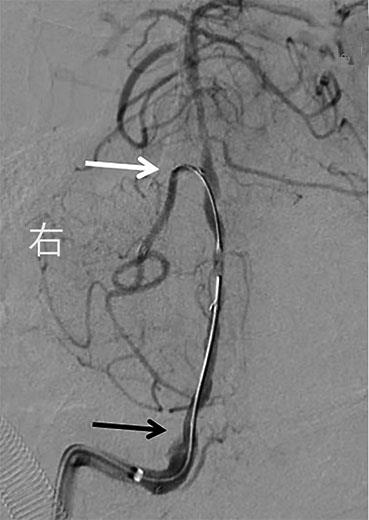

• 挽救性支架植入对取栓困难的脑动脉栓塞开通效果

2022, 47(7):779-783. DOI: 10.13406/j.cnki.cyxb.003067

摘要:目的 探究急性脑栓塞取栓失败和神经介入术中发生医源性脑动脉栓塞后补救性支架植入术的开通效果。方法 回顾性分析2020年1月至2021年11月上海交通大学医学院附属第九人民医院6例脑栓塞取栓失败和4例医源性颅内中远端动脉栓塞、接受补救性支架植入术的患者临床信息,总结患者术后血管开通情况、术后24 h 支架内血流通畅情况、出血转化和预后等情况。结果 6例急性脑栓塞取栓失败,补救性支架植入后闭塞血管全部开通(modified thrombosis in cerebral infarction score,mTICI 2b~3),术后3例出血转化(1例PH2型,2例HI2型),术后24 h支架内血流通畅5例(83%),1例未行血管造影复查;3例患者住院期间死亡。4例医源性中远端动脉闭塞中,1例为原发病为椎基底动脉高度狭窄,支架置入术中发生右侧小脑前下动脉闭塞,补救性支架置入后完全开通,术后24 h复查所有支架通畅,无脑出血,3个月预后良好,改良Rankin量表(modified Rankin score,mRS)评分1分;3例原发病为大脑中动脉栓塞,取栓术中出现同侧大脑前动脉分支闭塞,补救性支架植入后完全开通,其中1例术后24 h头颅计算机体层血管成像(computed tomography angiography,CTA)可见支架通畅,合并片状出血转化(HI2型),2例因为病重未行血管复查。结论 补救性支架植入可以快速开通取栓失败以及医源性中远端动脉的栓塞,但是疗效和安全性需进一步研究。